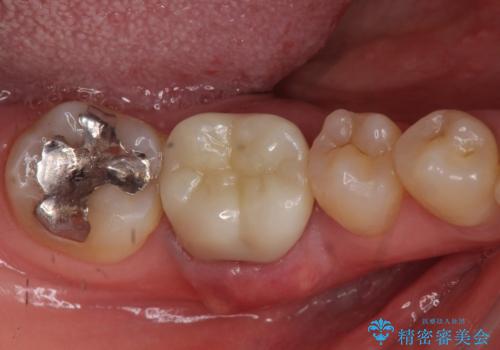

- 他院で虫歯治療に伴い初めての神経の治療を行ったところ、神経の治療自体10回以上通った上に抜歯と言われたとのことでした。

初診時には歯肉が腫れており、膿が出ている状態でした。

また、根の詰め物が根尖孔外(根の先の外の骨の部分)に盛大に漏れ出しており、歯周ポケットと根尖病巣が交通しているような状態でした。